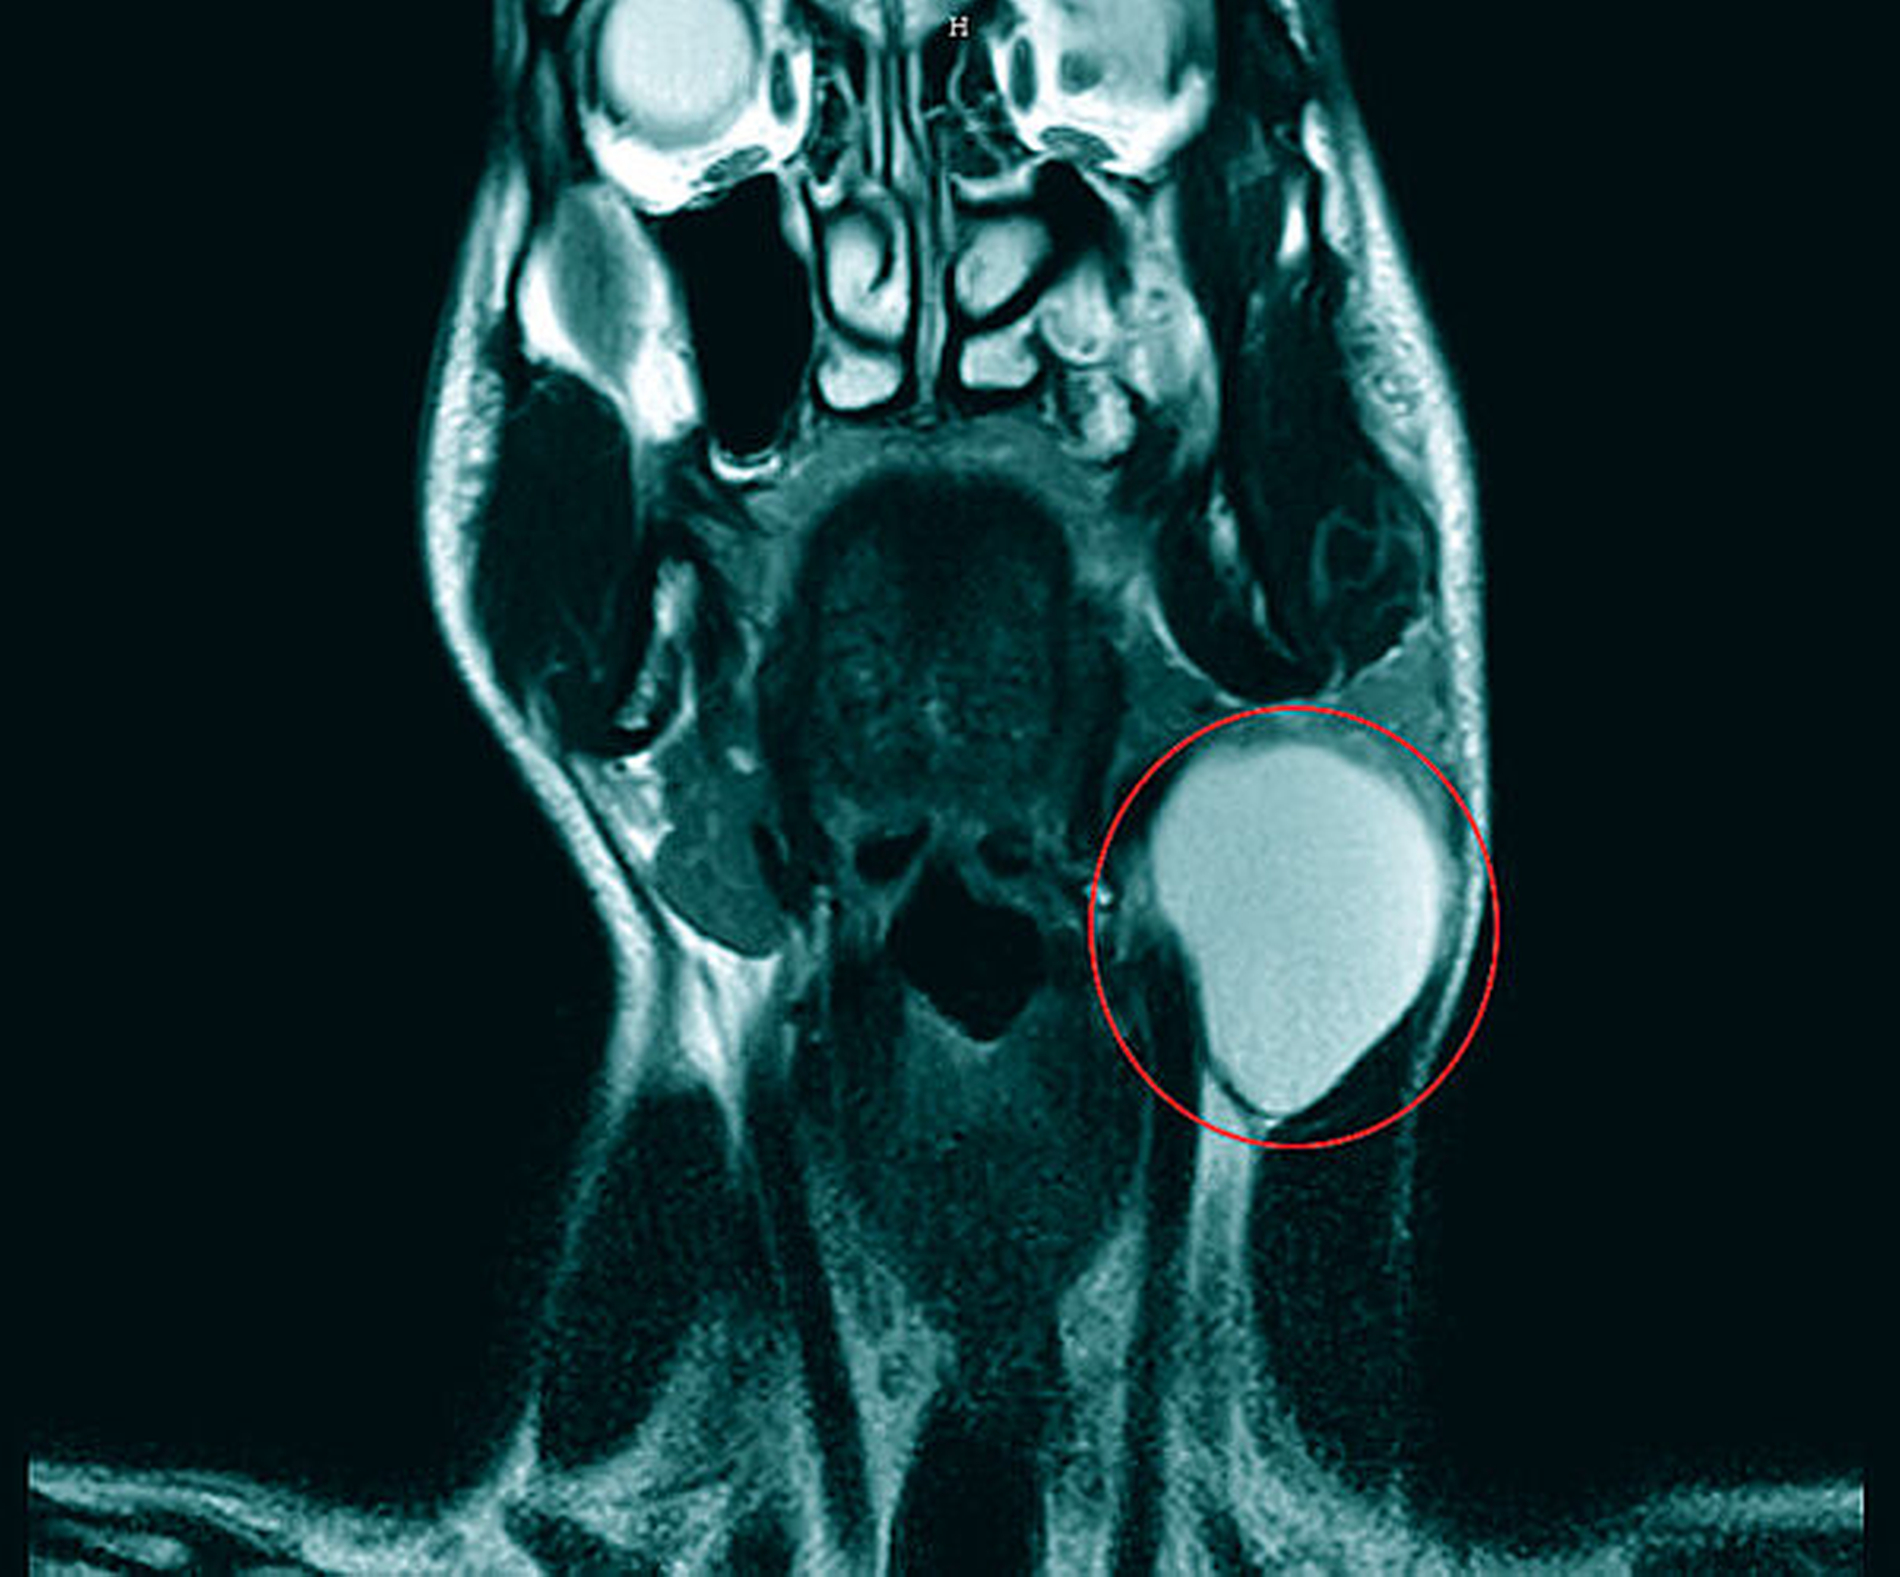

Zur weiteren Abklärung wurde eine Magnetresonanz-Untersuchung initiiert. Es zeigte sich eine glatt berandete, T2-hyperintense Raumforderung zervikal links auf Höhe der Epiglottis. Eine Infiltration der benachbarten Strukturen war nicht ersichtlich (Abbildungen 2 bis 4).